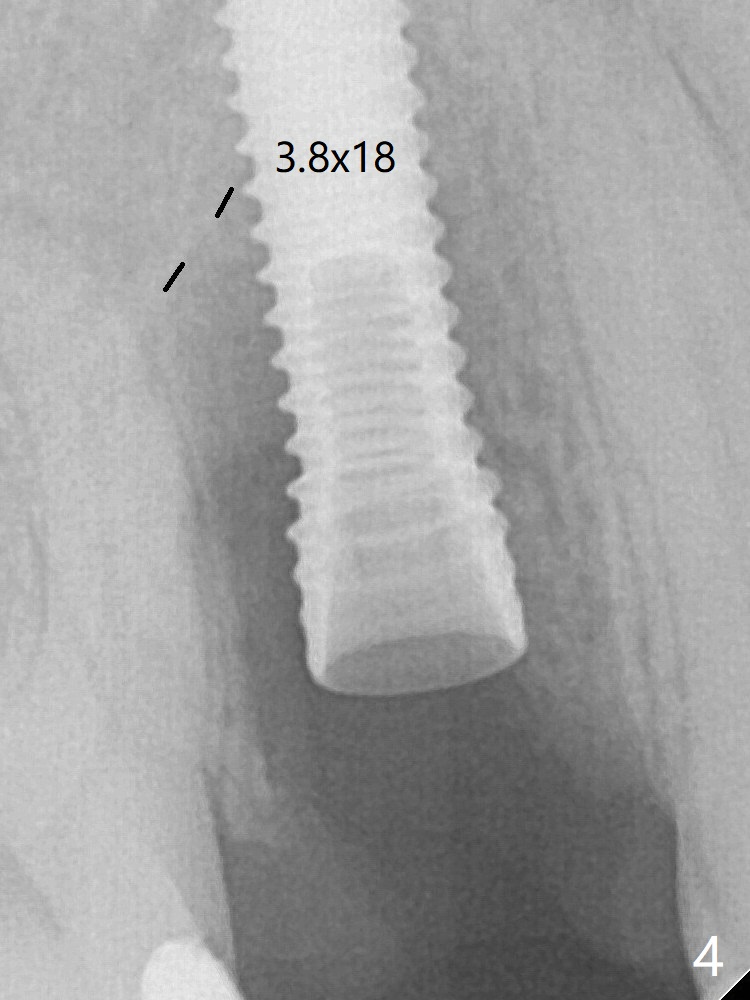

A 3.8x18 mm (definitive) implant is placed with <40 Ncm with the implant plateau apical to the lingual crest (Fig.4 (dashed line: upper border of the buccal defect)).  The buccal plate defect is repaired by Vanilla Graft (Fig.6 *) before and after insertion of a 4.5x4(3) mm abutment.  The buccal plate defect seems to being repaired 4 months postop (Fig.7).  The defect repair is close to completion 8 months post cementation (Fig.8).